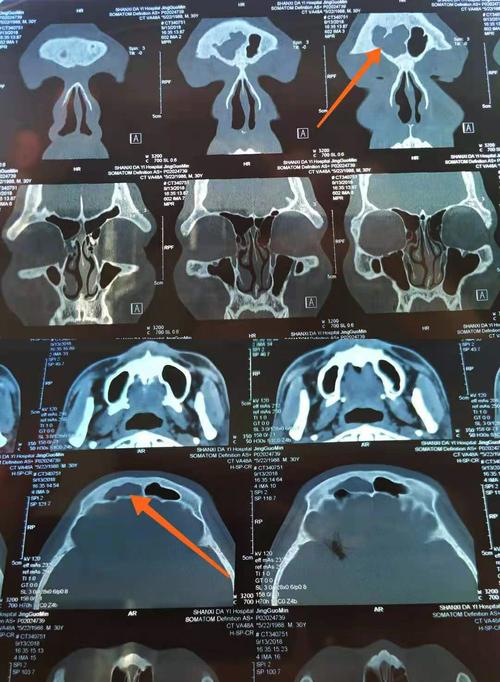

邹女士患额窦炎多方治疗无效果,听申力医生建议手术后终于治愈

源自网络上颌窦炎可产生面颊部疼痛,牙痛和头痛;额窦炎有前额部疼痛

额窦炎ct

额窦炎ct图片

额窦炎ct诊断图片

额窦炎ct表现图片